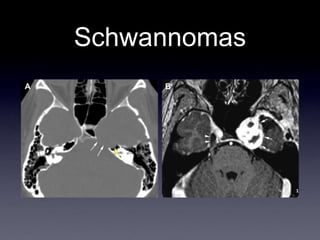

Schwannomas